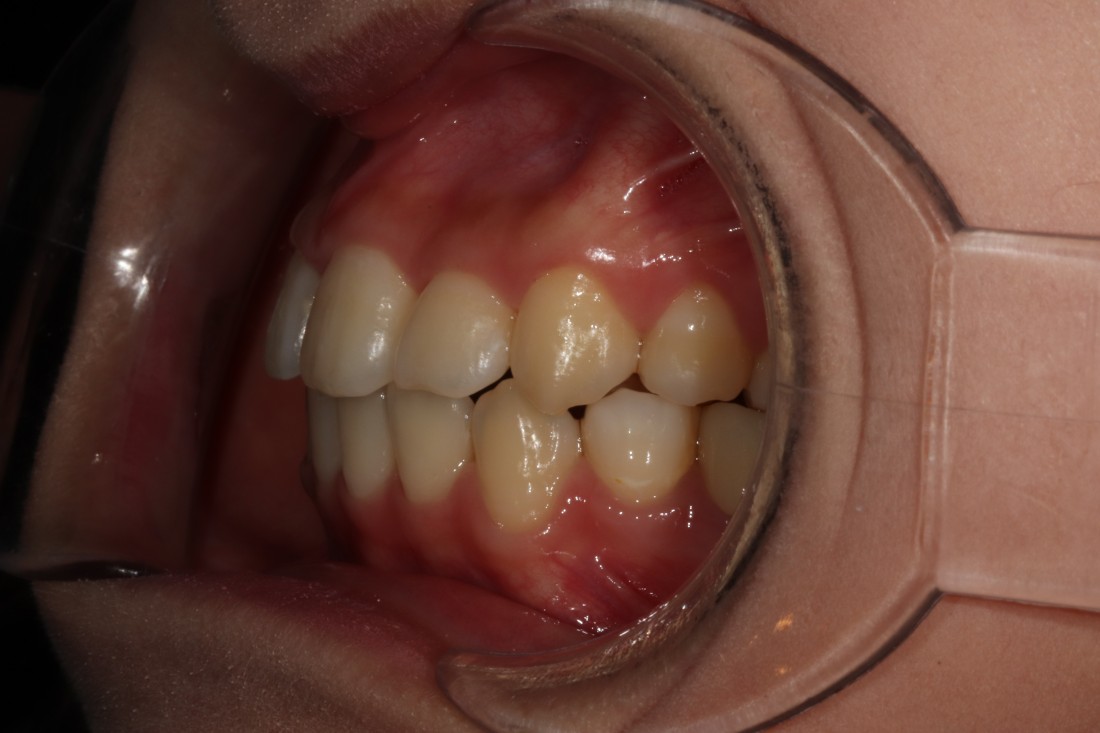

광주 성인 교정치과에서

충치치료와 교정진료를 동시에 받으신

성인 여성 환자분의 케이스입니다.

충치치료 전에는 은색 보철물이 있던 자리에

교정진료의 마무리와 동시에

치아색 보철물을 씌워서

치아교정 + 충치치료를 동시에 진행하였습니다.

광주 성인 치아교정의 경우

충치치료의 시기를 잘 판단하여

성공적인 진료를 완성할 수 있기 때문에

분과별 전문의가 협진하는

광주 성인 교정치과를 선택하시는 것이 좋습니다.